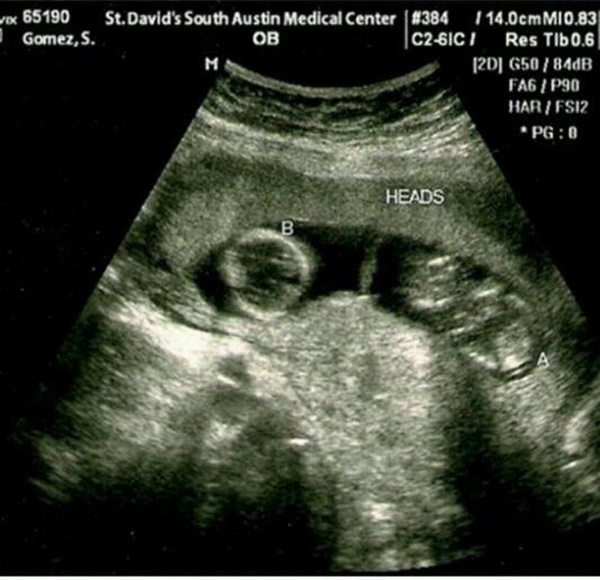

TMZ publicaba unos días una imagen de una ecografía que no dejaba lugar a dudas, al pertenecer a una paciente llamada 'Gómez, S'. Ante la locura de las adolescentes de medio mundo, la ecografía mostraba como una supuesta Selena Gomez está embarazada de Justin Bieber, de gemelos (nada más y nada menos, papelón total). Y más tras saber que la pareja teen más popular del planeta había vuelto unos días antes y que durante su reencuentro a la propia Selena se le habían hecho pruebas por jaquecas y mareos.